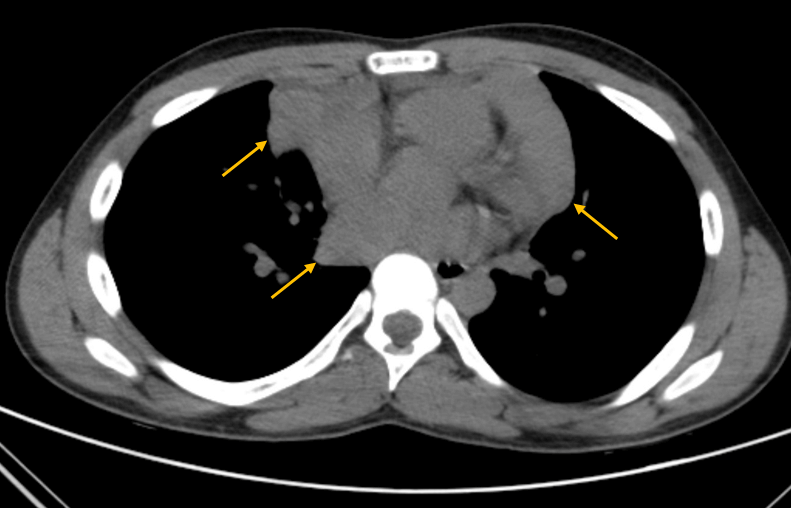

A 14-year-old boy, with a previous history of allergic rhinitis, presented to the PED due to sudden onset of a left cervical swelling. He had a six-month history of dry cough and for the last three days he had also been complaining of dyspnoea and thoracalgia (sudden onset during sleep), which was worsening and now radiating to the right shoulder. No other signs or symptoms. On examination, there was a mass on the anterior left cervical triangle, with approximately 2x3 cm, fixed to the muscle below, firm and non-tender. Laboratory studies revealed normal hemogram (hemoglobin 14.8 g/dL, leucocytes 9.3x1^3uL, neutrophils 68.2%, lymphocytes 21.6%) and elevated C-reactive protein (3.28 mg/dL, N<0.5 mg/dL) and lactate dehydrogenase (1113 U/L, N<230 U/L). The chest x-ray showed a large mediastinal mass (Figure 1) in the middle mediastinum, with a 15.13 cm width, prompting an urgent referral to Oncology. CT scan revealed several lymphoid masses, cervical bilateral (the largest on the left, 4x3 cm) (Figure 2) and at the anterior mediastinum (8.5x5.5cm, 7.5x4cm) (Figure 3). Abdominal CT was normal.

Figure 3. Thorax CT scan: multiple mediastinal lymphoid masses (8.5x5.5 cm, 7.5x4 cm).